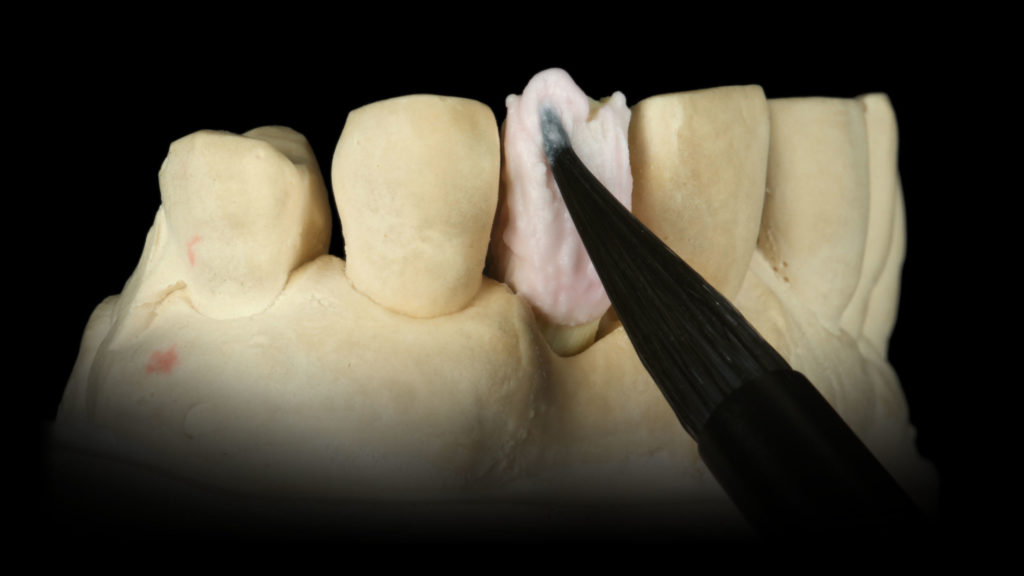

Zunächst wurde das Oberkieferfrontzahnsegment mitsamt dem darin befindlichen Abformpfosten und aufgeschraubten Laboranalog ausgegossen. Nach dem Aushärten des Gipsmodells konnte ein Abutment aufgeschraubt und ein diagnostisches Wax-up modelliert werden. Das Emergenzprofil wurde dabei entsprechend des gewünschten Austrittsprofils am Gipsmodell konturiert (Abb. 3a). Daraufhin wurde entsprechend dieser Konturierung eine abnehmbare Zahnfleischmaske angefertigt. Allerdings zeigte sich, dass sich das Wax-up mit aufgesetzter weichbleibender Zahnfleischmaske nicht mehr exakt reponieren ließ (Abb. 3b und c). Aus diesem Grund musste die abnehmbare Zahnfleischmaske entsprechend der zuvor festgelegten Kontur des Austrittsprofils beschliffen werden, sodass sich das Wax-up wieder exakt zurücksetzen ließ (Abb. 4a bis c). Eine abnehmbare Zahnfleischmaske ist hilfreich, um den exakten Sitz des Implantataufbaus auf dem Implantats überprüfen zu können.